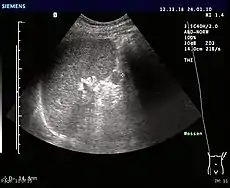

Accessory spleens may undergo hypertrophy after splenectomy[15] Very rarely, it may cause bleeding (pictured).[16]

16. Note: The case is possibly splenosis rather than an accessory spleen:

Maki, Takehiro; Omi, Makoto; Ishii, Daisuke; Kaneko, Hiroyuki; Misu, Kenjiro; Inomata, Hitoshi; Tateno, Masatoshi; Nihei, Kazuyoshi (2015). "Spontaneous hemorrhage from splenic tissue 13 years after total splenectomy: report of a case". Surgical Case Reports. 1 (1): 91. doi:10.1186/s40792-015-0099-0. ISSN 2198-7793. PMC 4593983. PMID 26943415.